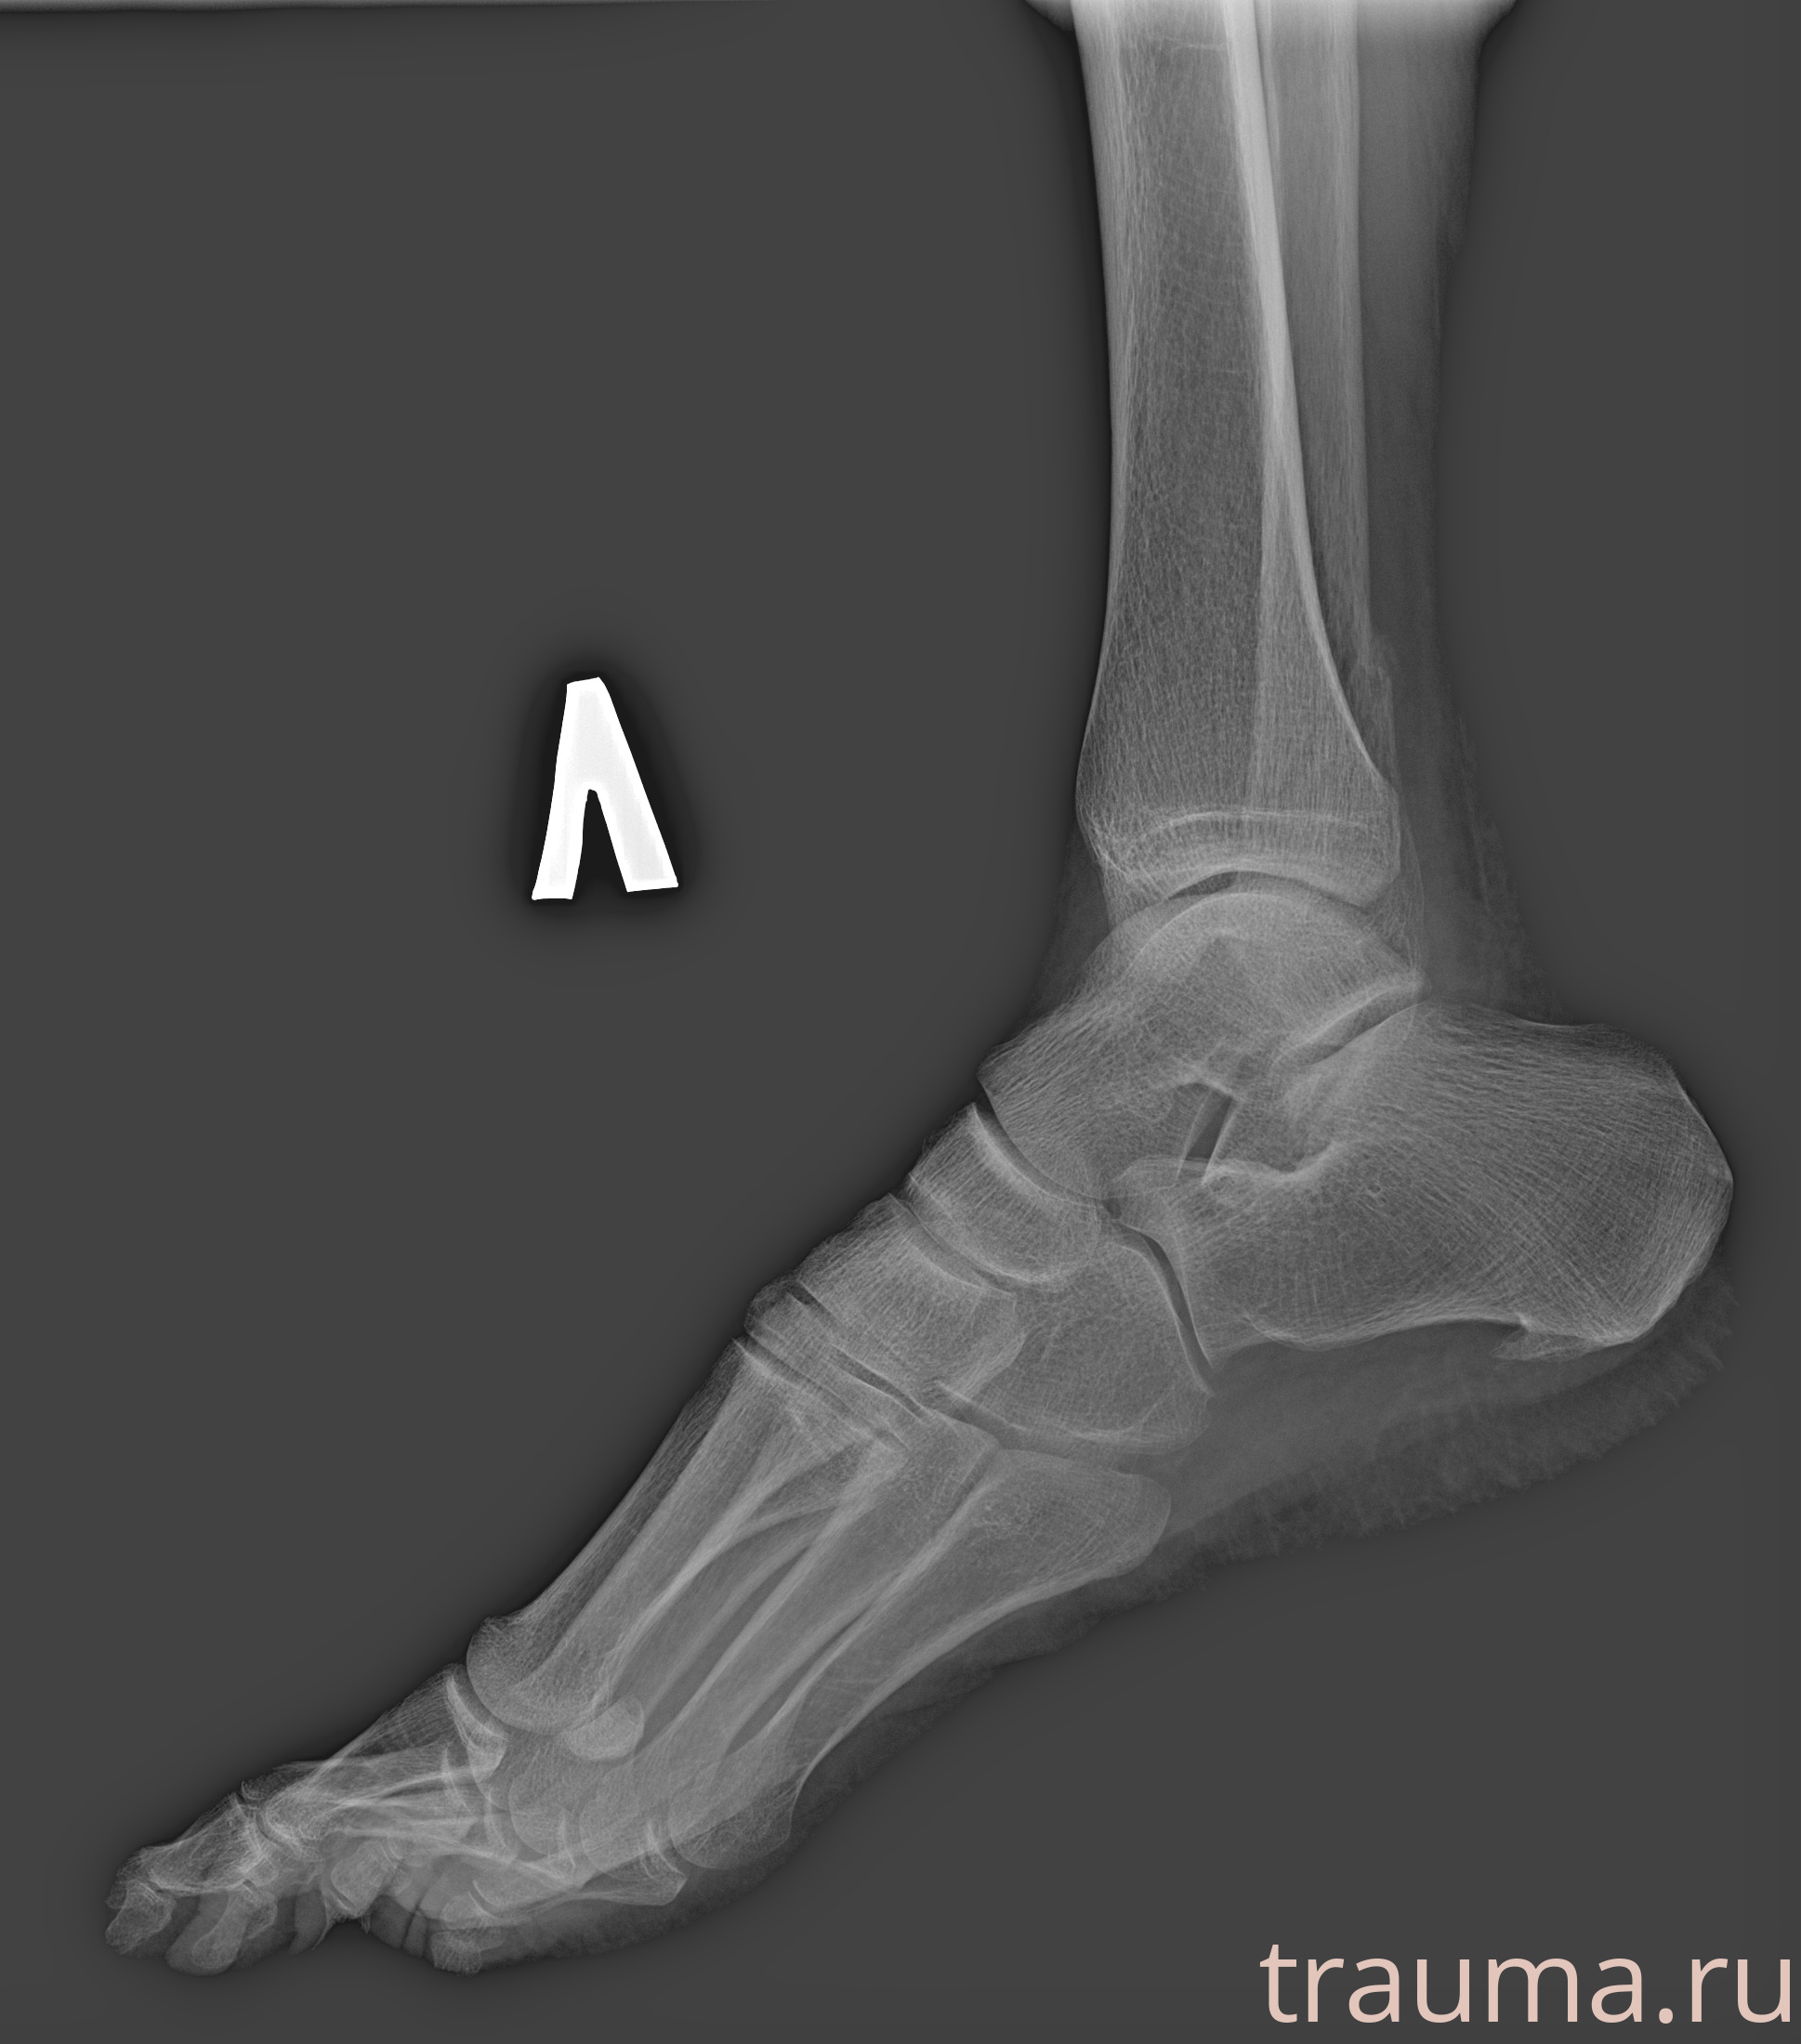

Рентгенограммы

Рентген на дому: по вашему адресу приезжает врач-рентгенолог, травматолог-ортопед с мобильным рентгеновским аппаратом, проводит диагностику травмы или заболевания, делает необходимые рентгенограммы, дает рекомендации по дальнейшему лечению. Получить качественные снимки в домашних условиях возможно благодаря уникальной методике, разработанной МосРентген Центром для института  Склифосовского

Яркость: 1   Контраст: 1   Инвертировать: 0 Увеличение: 1

Перетаскивайте мышь вверх/вниз для контраста, влево/право для яркости. Прокрутка колесом изменяет масштаб. Нажмите Сбросить для возврата к исходному изображению. При увеличении держите мышь в той области, которую хотите рассмотреть.